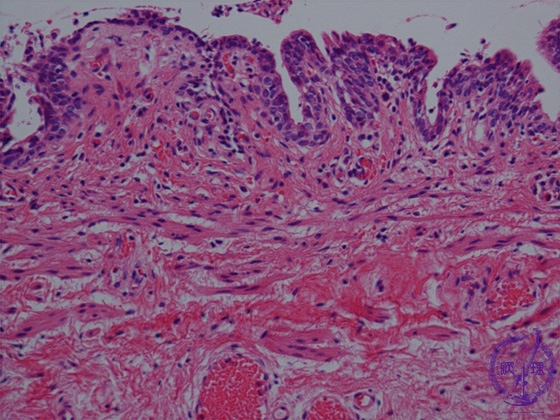

- (1)Hirschprung disease

Microscopic view: While nerve fibers are present (arrows), ganglion cells are not.